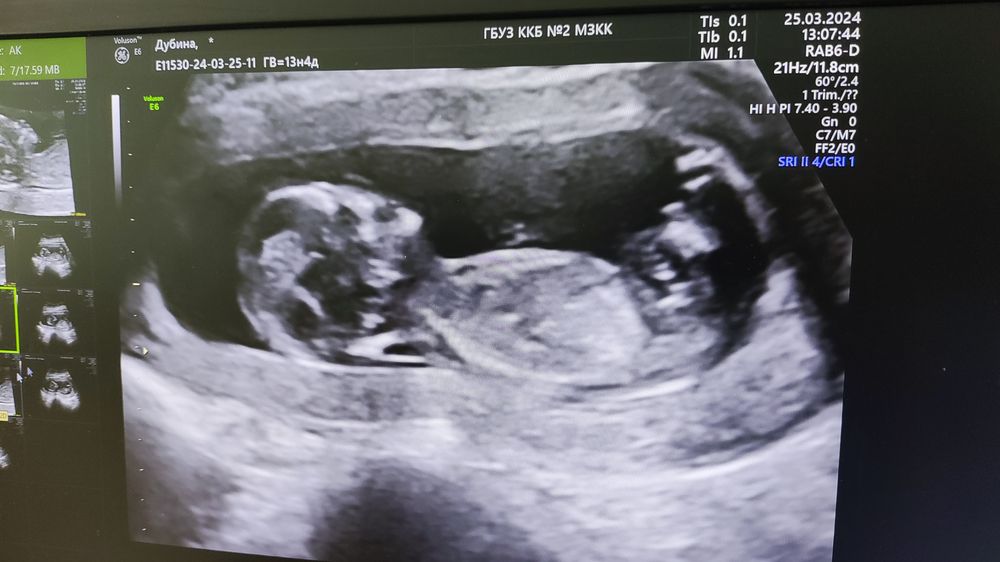

Фото с УЗИ

Вот мы и прошли 1 скринг официально и полностью) кровь сдали, УЗИ сделали. Малыш долго не хотел показывать личико, пришлось погулять по этажам)

По показателям все отлично. Разрешили сделать фото с экрана. Ну и вообщем по нему с полом все ясно😉

По УЗИ уже 13,4